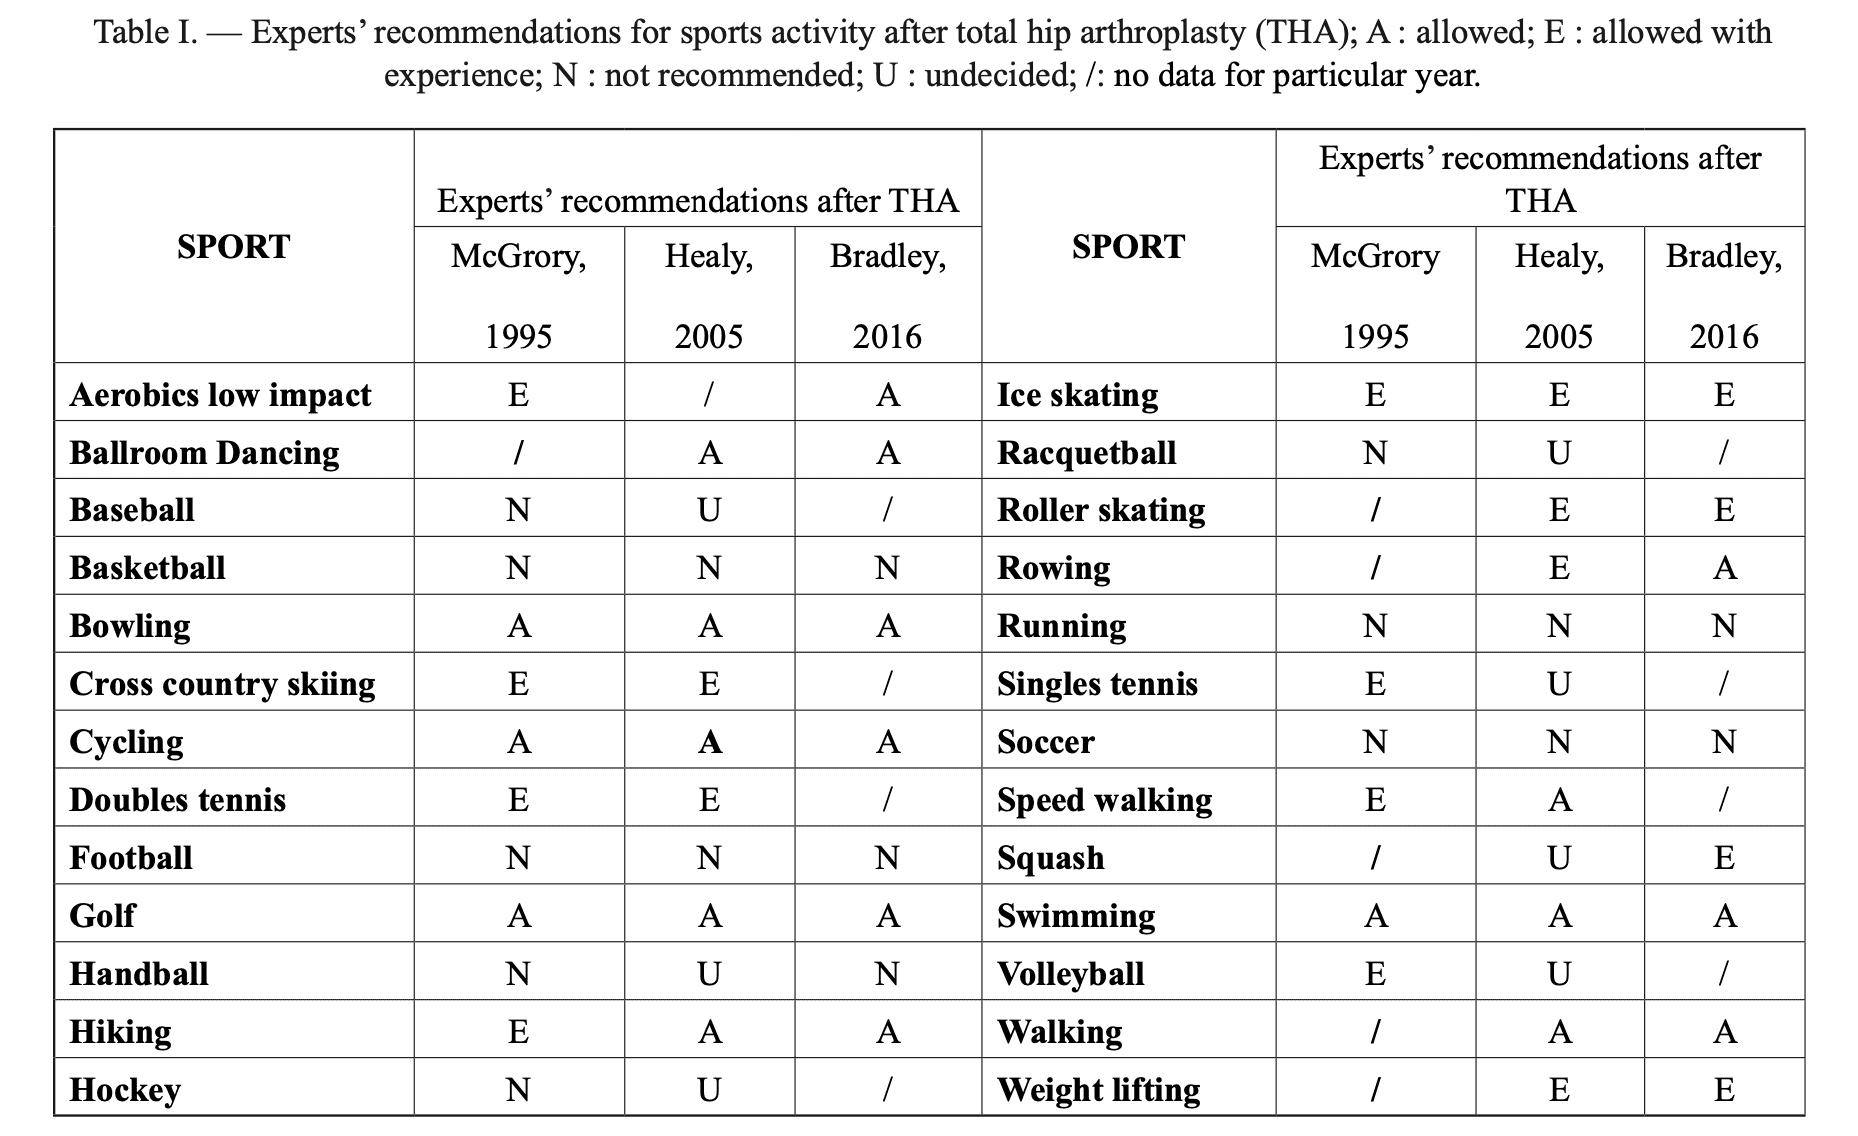

Oljaca 等人,2018 年对共识文件中有关 THA 后 RTS 的证据进行了分析,并总结如下表所示。 可以看到,在许多体育项目中,有关 RTS 的证据多年来一直在变化。

这个汇总表有话要说。 2022 年,本德测量了活体关节接触力和扭转力矩,发现保龄球等被认为是低冲击力的活动,与高冲击力的足球相比,会产生更高的关节接触力和扭转力矩。 此外,他们还发现体重和体重指数也会影响日常活动中的这些力。